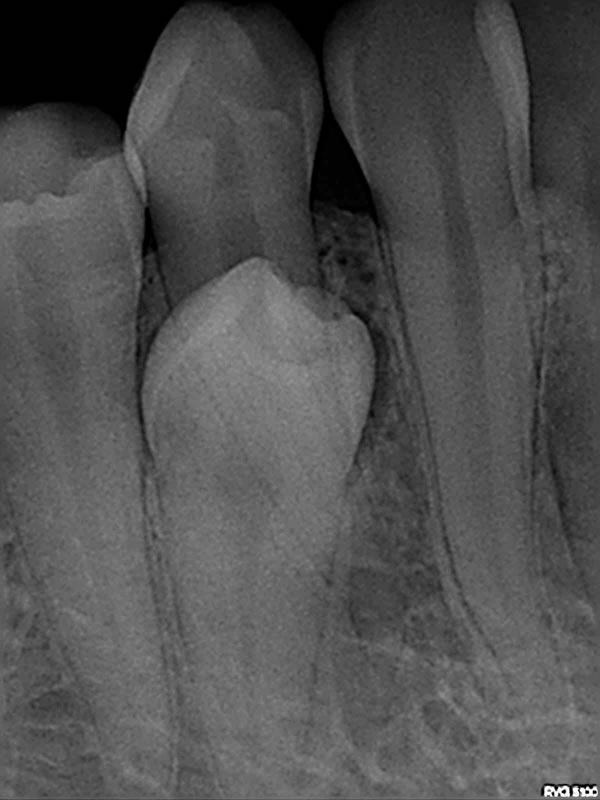

RTG / RVG

Digitalna tehnika snimanja zuba rtg /rvg aparatom omogućava nam trenutni prikaz stanja zuba i čeljusne kosti. Ordinacija je opremljena potpuno novim uređajem za rtg snimanje zuba sa minimalnim dozama ionizirajućeg zračenja. Kodak 2200 i Kodak 5100 i digitalnim senzorom za intraoralne snimke zuba.

Povećana pouzdanost dijagnostike

Kodakov visoko frekventni generator omogućuje postizanje snimaka vrlo visoke kvalitete, dok istovremeno maksimalno smanjuje izloženost radijaciji. Sa žarišnom točkom od 0.7 mm i preciznim usmjerenim zračenjem, Kodak 2200 pruža visoko kvalitetnu i preciznu snimku sa raznolikim stupnjem sivog spektra.

Maksimalna kvaliteta slike – Minimalna izloženost zračenju

Ovisno o anatomskom području slikanja, tjelesnoj težini pacijenta i vrsti filma ili senzora koji se koristi, Kodak 2200 sistem automatski podešava vrstu i vrijeme ekspozicije zračenja. Ta preciznost omogućuje maksimalnu redukciju izloženosti radijaciji.